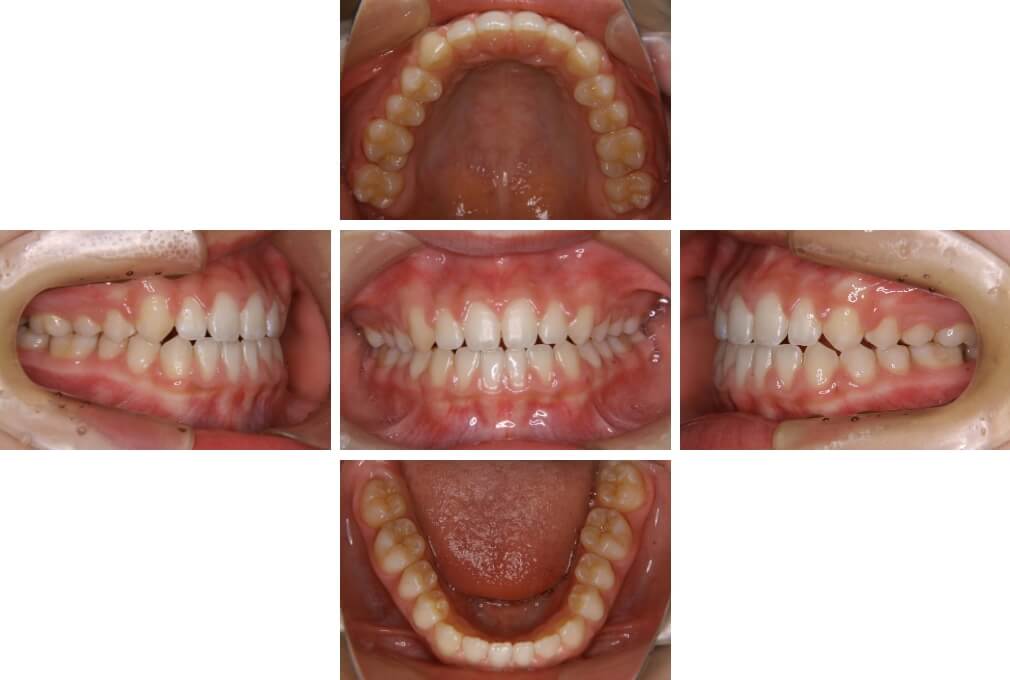

CASE:04

アングルⅢ級傾向を持つ叢生

初診時年齢 22歳

性別 女性

治療費の目安 105万円程度(治療開始時)

上顎右側犬歯が唇側に転位していることを主訴に県内歯科医院から紹介来院された。骨格的にはⅢ級傾向で上顎右側犬歯が唇側転位となり、側切歯が口蓋側に転位していた。下顎前歯が叢生になっていることも相まって上下の正中線は右側に大きくずれていた。アングルⅢ級傾向を持つ上下顎前歯部叢生と診断した。

上下顎小臼歯を抜歯していただき上顎舌側、下顎唇側マルチブラケット装置を使用して動的治療を行った。矯正用ゴムの使用など協力状態も良く、正中線の大きな移動があったのも関わらず2年10カ月で装置を撤去し保定へ移行した。保定移行後14年が経過し、ご息女の診察でご来院いただいていたことから、口腔内を拝見したが、下顎前歯のわずかなずれがあったものの大きな歯列の乱れはなく歯列は安定していた。動的治療期間2年10カ月間。

治療前

22歳6か月

治療後

動的治療期間2年10カ月間

25歳6か月

治療終了

動的治療終了後2年2カ月

28歳8か月

14年経過

動的治療終了後14年7カ月

40歳1か月